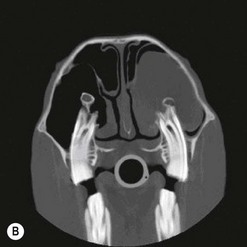

image image image

Fig. 13.43 Radiograph (A) and CT images (B and C) of a compound odontoma in a 2-year-old TB colt.

(Images courtesy of J. Easley.)